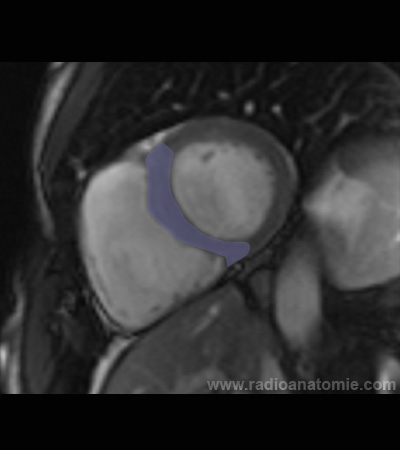

Radioanatomie et plans de coupe en IRM cardiaque

Ventricule gauche

Ventricule droit

Septum interventriculaire